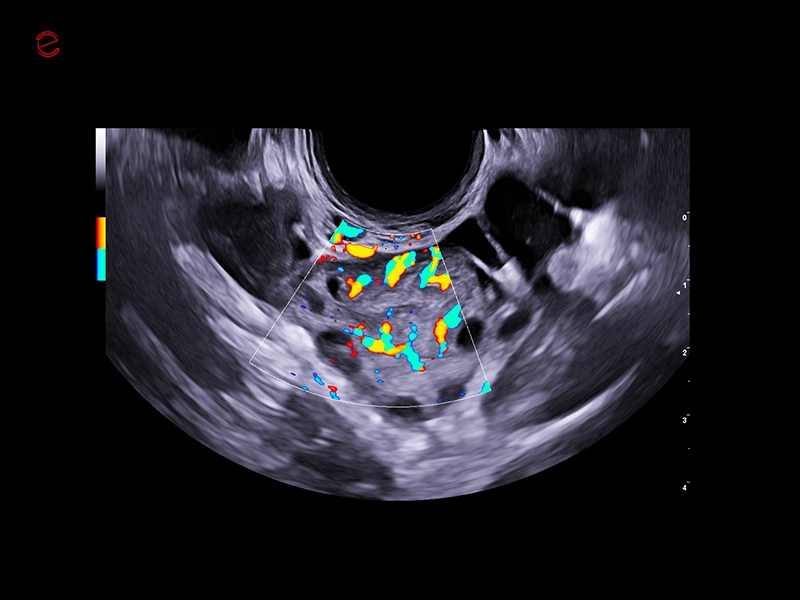

MyLab™C25 - Mioma PD

MyLab™C25 - Mioma PD